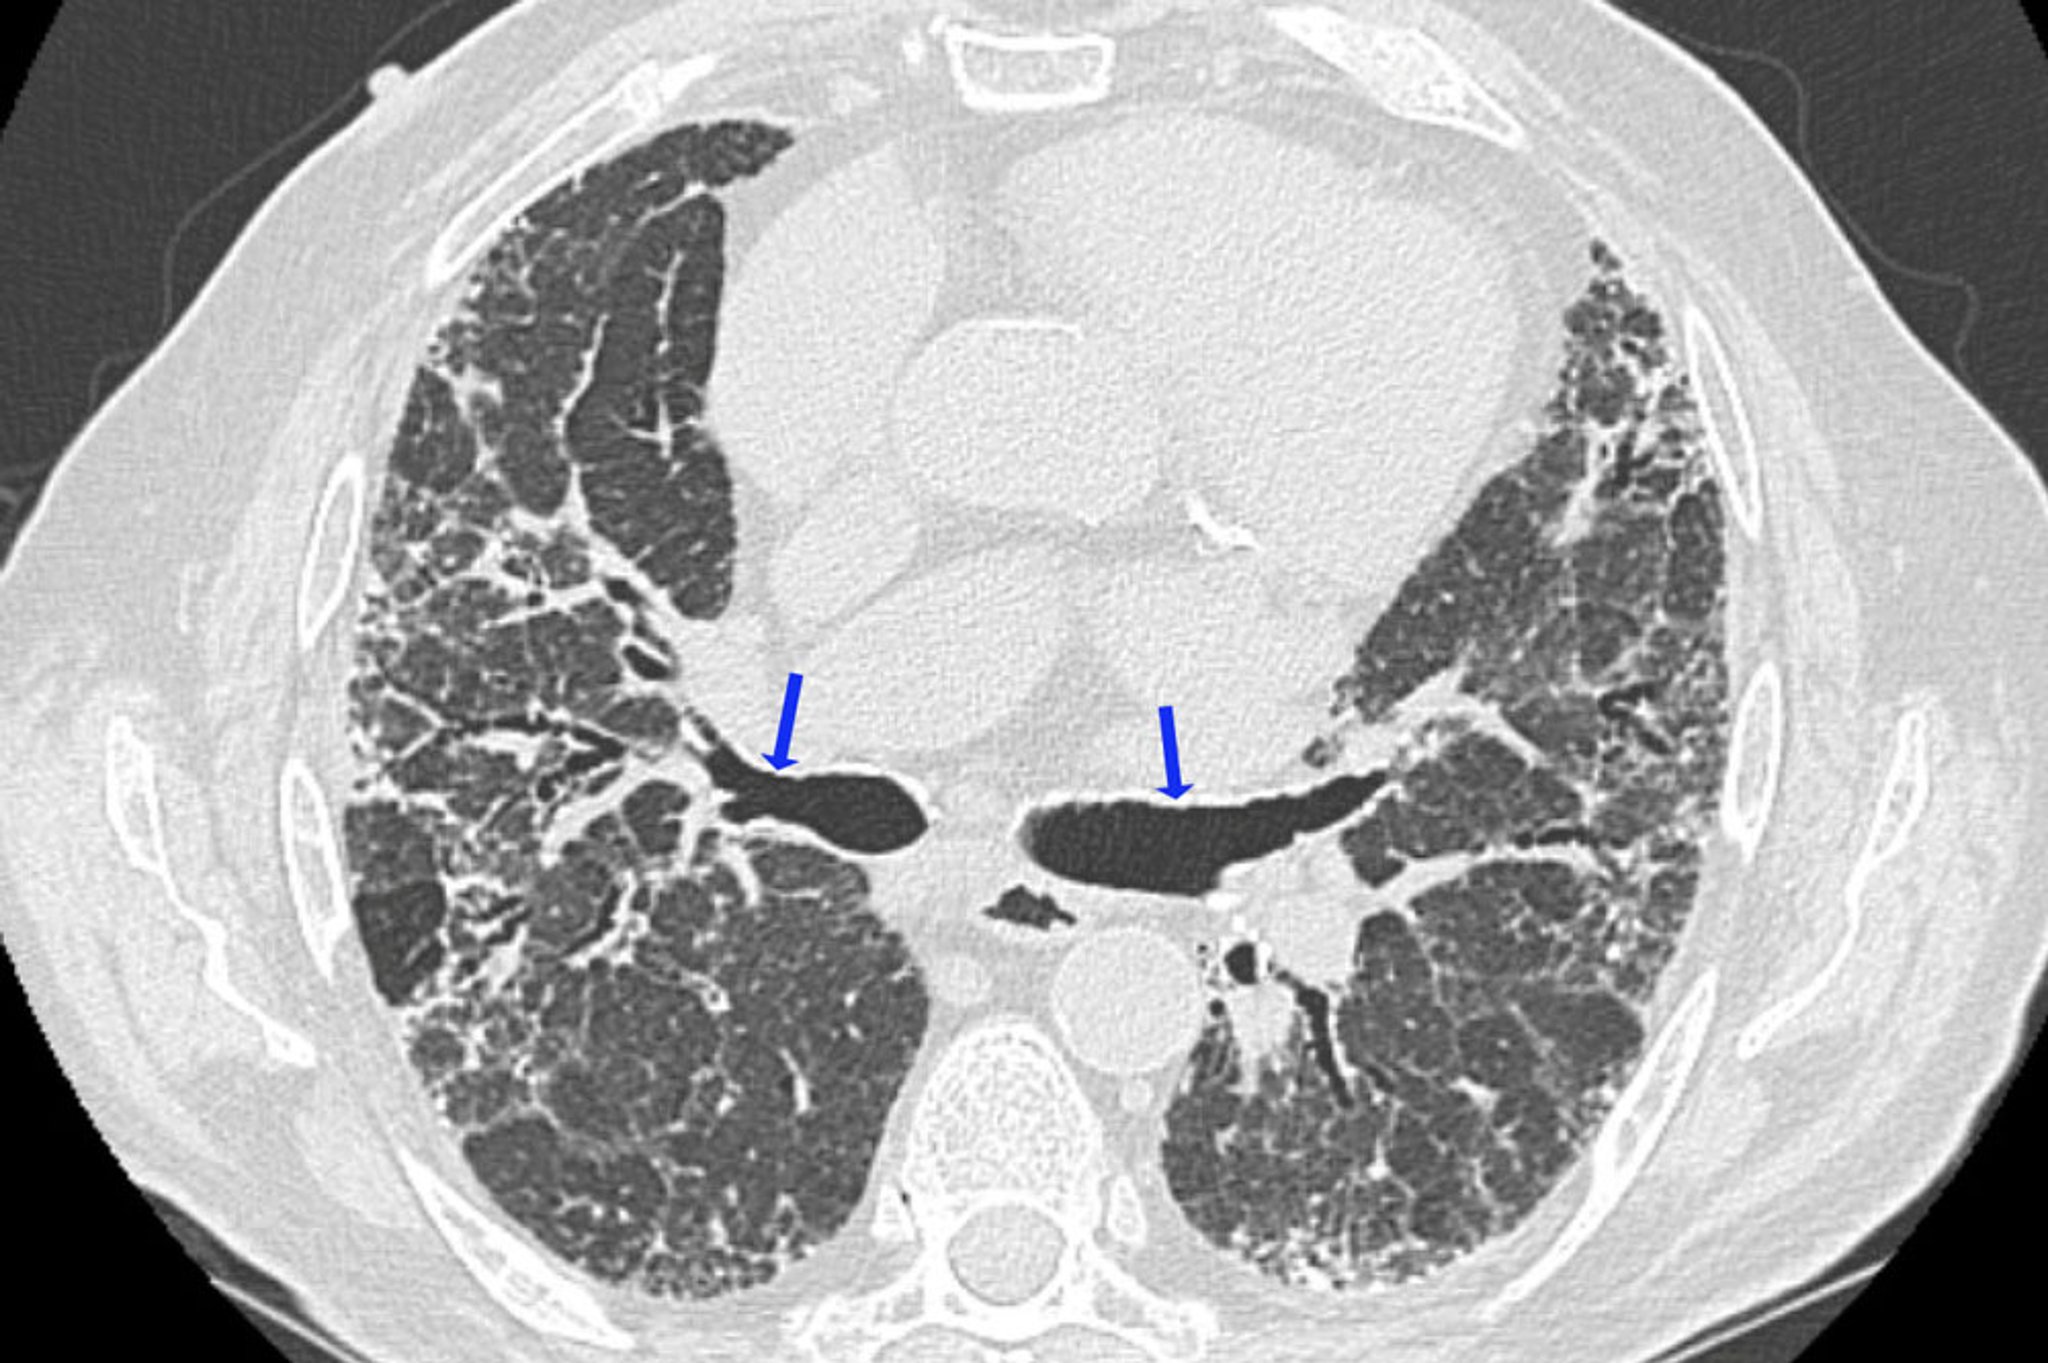

Pneumonite crônica de hipersensibilidade

Esta TC de alta resolução mostra achados de fibrose, com reticulação irregular e bronquiectasia por tração (setas). Áreas de menor densidade pulmonar são compatíveis com as regiões de obstrução das vias respiratórias. Essa combinação de achados é sugestiva de pneumonite de hipersensibilidade.

Imagem cedida por cortesia de Joyce Lee, MD, MAS.